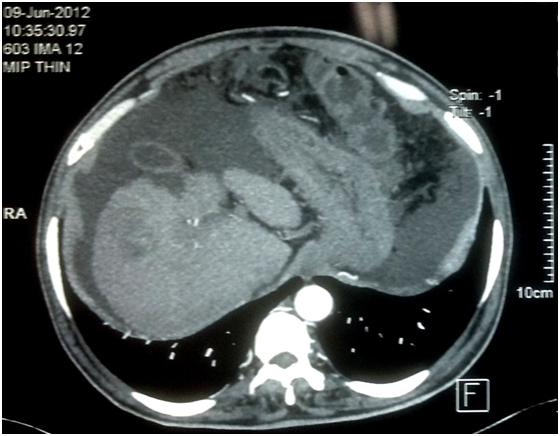

A 62 year male presented to our outpatient department with progressive abdominal distension for 1 month. He denied having fever, abdominal pain, jaundice, gastrointestinal bleed or encephalopathy. He did not smoke, consume alcohol, took any other drug or had any other illness. He lost 5Kg body weight during this illness. Investigations at presentation revealed haemoglobin of 12.3gm/dl (normal:13.5-17), total leucocyte count 9500/μL (normal: 4,000-10,000), platelet count of 152,000/μL (normal:150,000-400,000), prothrombin time 17 sec (control 13.1), creatinine 1.1mg/dL (normal: 0.8-1.4), albumin 2.6g/dL (normal: 3.5-5.4), bilirubin 1.8 mg/dL (normal: 0.3-1.5) and serum alpha-fetoprotein 4.4 ng/ml. MELD score was 13. Etiologic workup for cirrhosis was unrevealing. Abdominal ultrasound showed a shrunken nodular liver with a space occupying lesion in the right lobe of liver, dilated portal vein, splenomegaly and ascites. Upper gastrointestinal tract endoscopy showed small esophageal varices. Dynamic computed tomography scan of abdomen showed irregular atrophic liver with a rounded lesion of size 5.6X4.8 cm in segment V enhancement in the arterial phase (Figure 1) and washout in the portal-venous phase (Figure 2). Performance status was 3 on ECOG scale.

Figure 1 Arterial phase of computed tomography scan of abdomen showed irregular atrophic liver with an enhancing rounded lesion of size 5.6 X 4.8 cm in segment V.